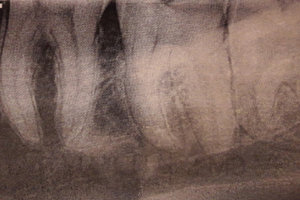

Здравствуйте! Подскажите пожалуйста, очень болит зуб вторую неделю! Нахожусь временно не в своём городе, тут гинеколог и стоматолог в одном лице. Скоро домой, договорился со своим лечащим врачом, примет по приезду 28/02, но боюсь не доживу, каждый день всё больнее и больнее. Предложили вырвать его, но он не шатается, стот крепко без кариеса вылеченный. Жевательный зуб 7, под десной сначала был красным, теперь весь зуб странного, бледного цвета. Ноет сильно пью обезболивающее. Есть снимок. Помогите пожалуйста.